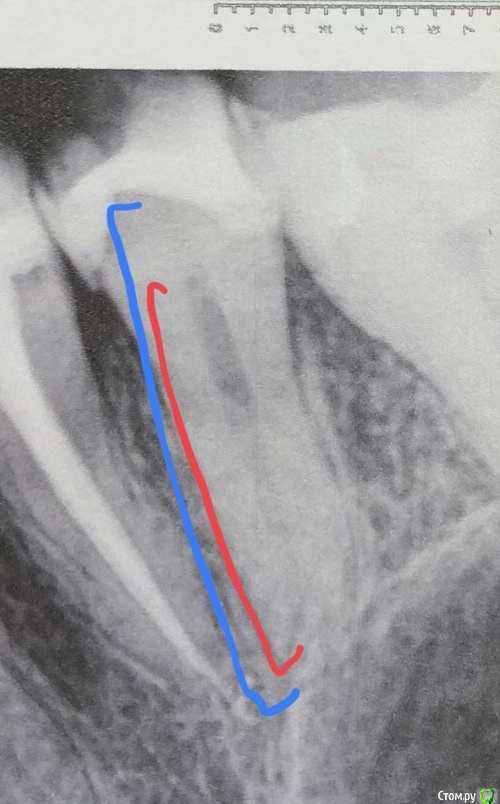

Olga2396 Опубликовано 10 октября, 2019 Автор Поделиться Опубликовано 10 октября, 2019 (изменено) Нерв начинается где красным? Или по данным снимкам начинается где синим отмечено?Можете объяснить? Мне кажется, что сам сосудисто-нервный пучок расположен где красным отмечено, но то что тень идёт до верха,как отмечено синим, я не знаю как объяснить... нервный пучок он же представлен из ткани а не обычной полости заполненной воздухом,где на верху мол он как бы меньше и типа якобы мы его уже задели, раз тень уже на снимке видна, как можно задеть,то,до чего ещё не дошёл?. Тогда если бы нерв находился выше как синим отмечено, откуда там быть дентину? Который бы защищал мой нерв,он же не из тонкой полоски состоит а эта твёрдая полость с большим количеством. Или я что то не так говорю? Я говорю своими словами как понимаю. Изменено 10 октября, 2019 пользователем Olga2396 Ссылка на комментарий

St. Опубликовано 10 октября, 2019 Поделиться Опубликовано 10 октября, 2019 Нерв начинается где красным? Или по данным снимкам начинается где синим отмечено? там где краснымВсе что выше это ткани зуба дентин и эмаль Ссылка на комментарий